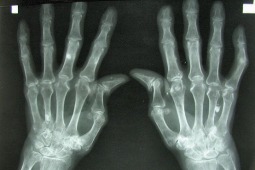

Reumatoidalne zapalenie stawów (w skrócie: RZS, dawna nazwa: gościec przewlekle postępujący, łac. polyarthritis reumatoidea, ang. rheumatoid arthritis w skrócie RA) – choroba reumatyczna o charakterze zapalnym i podłożu autoimmunologicznym. Charakteryzuje się nieswoistym zapaleniem stawów, zmianami pozastawowymi i powikłaniami układowymi. Przebiega z okresami remisji i zaostrzeń.